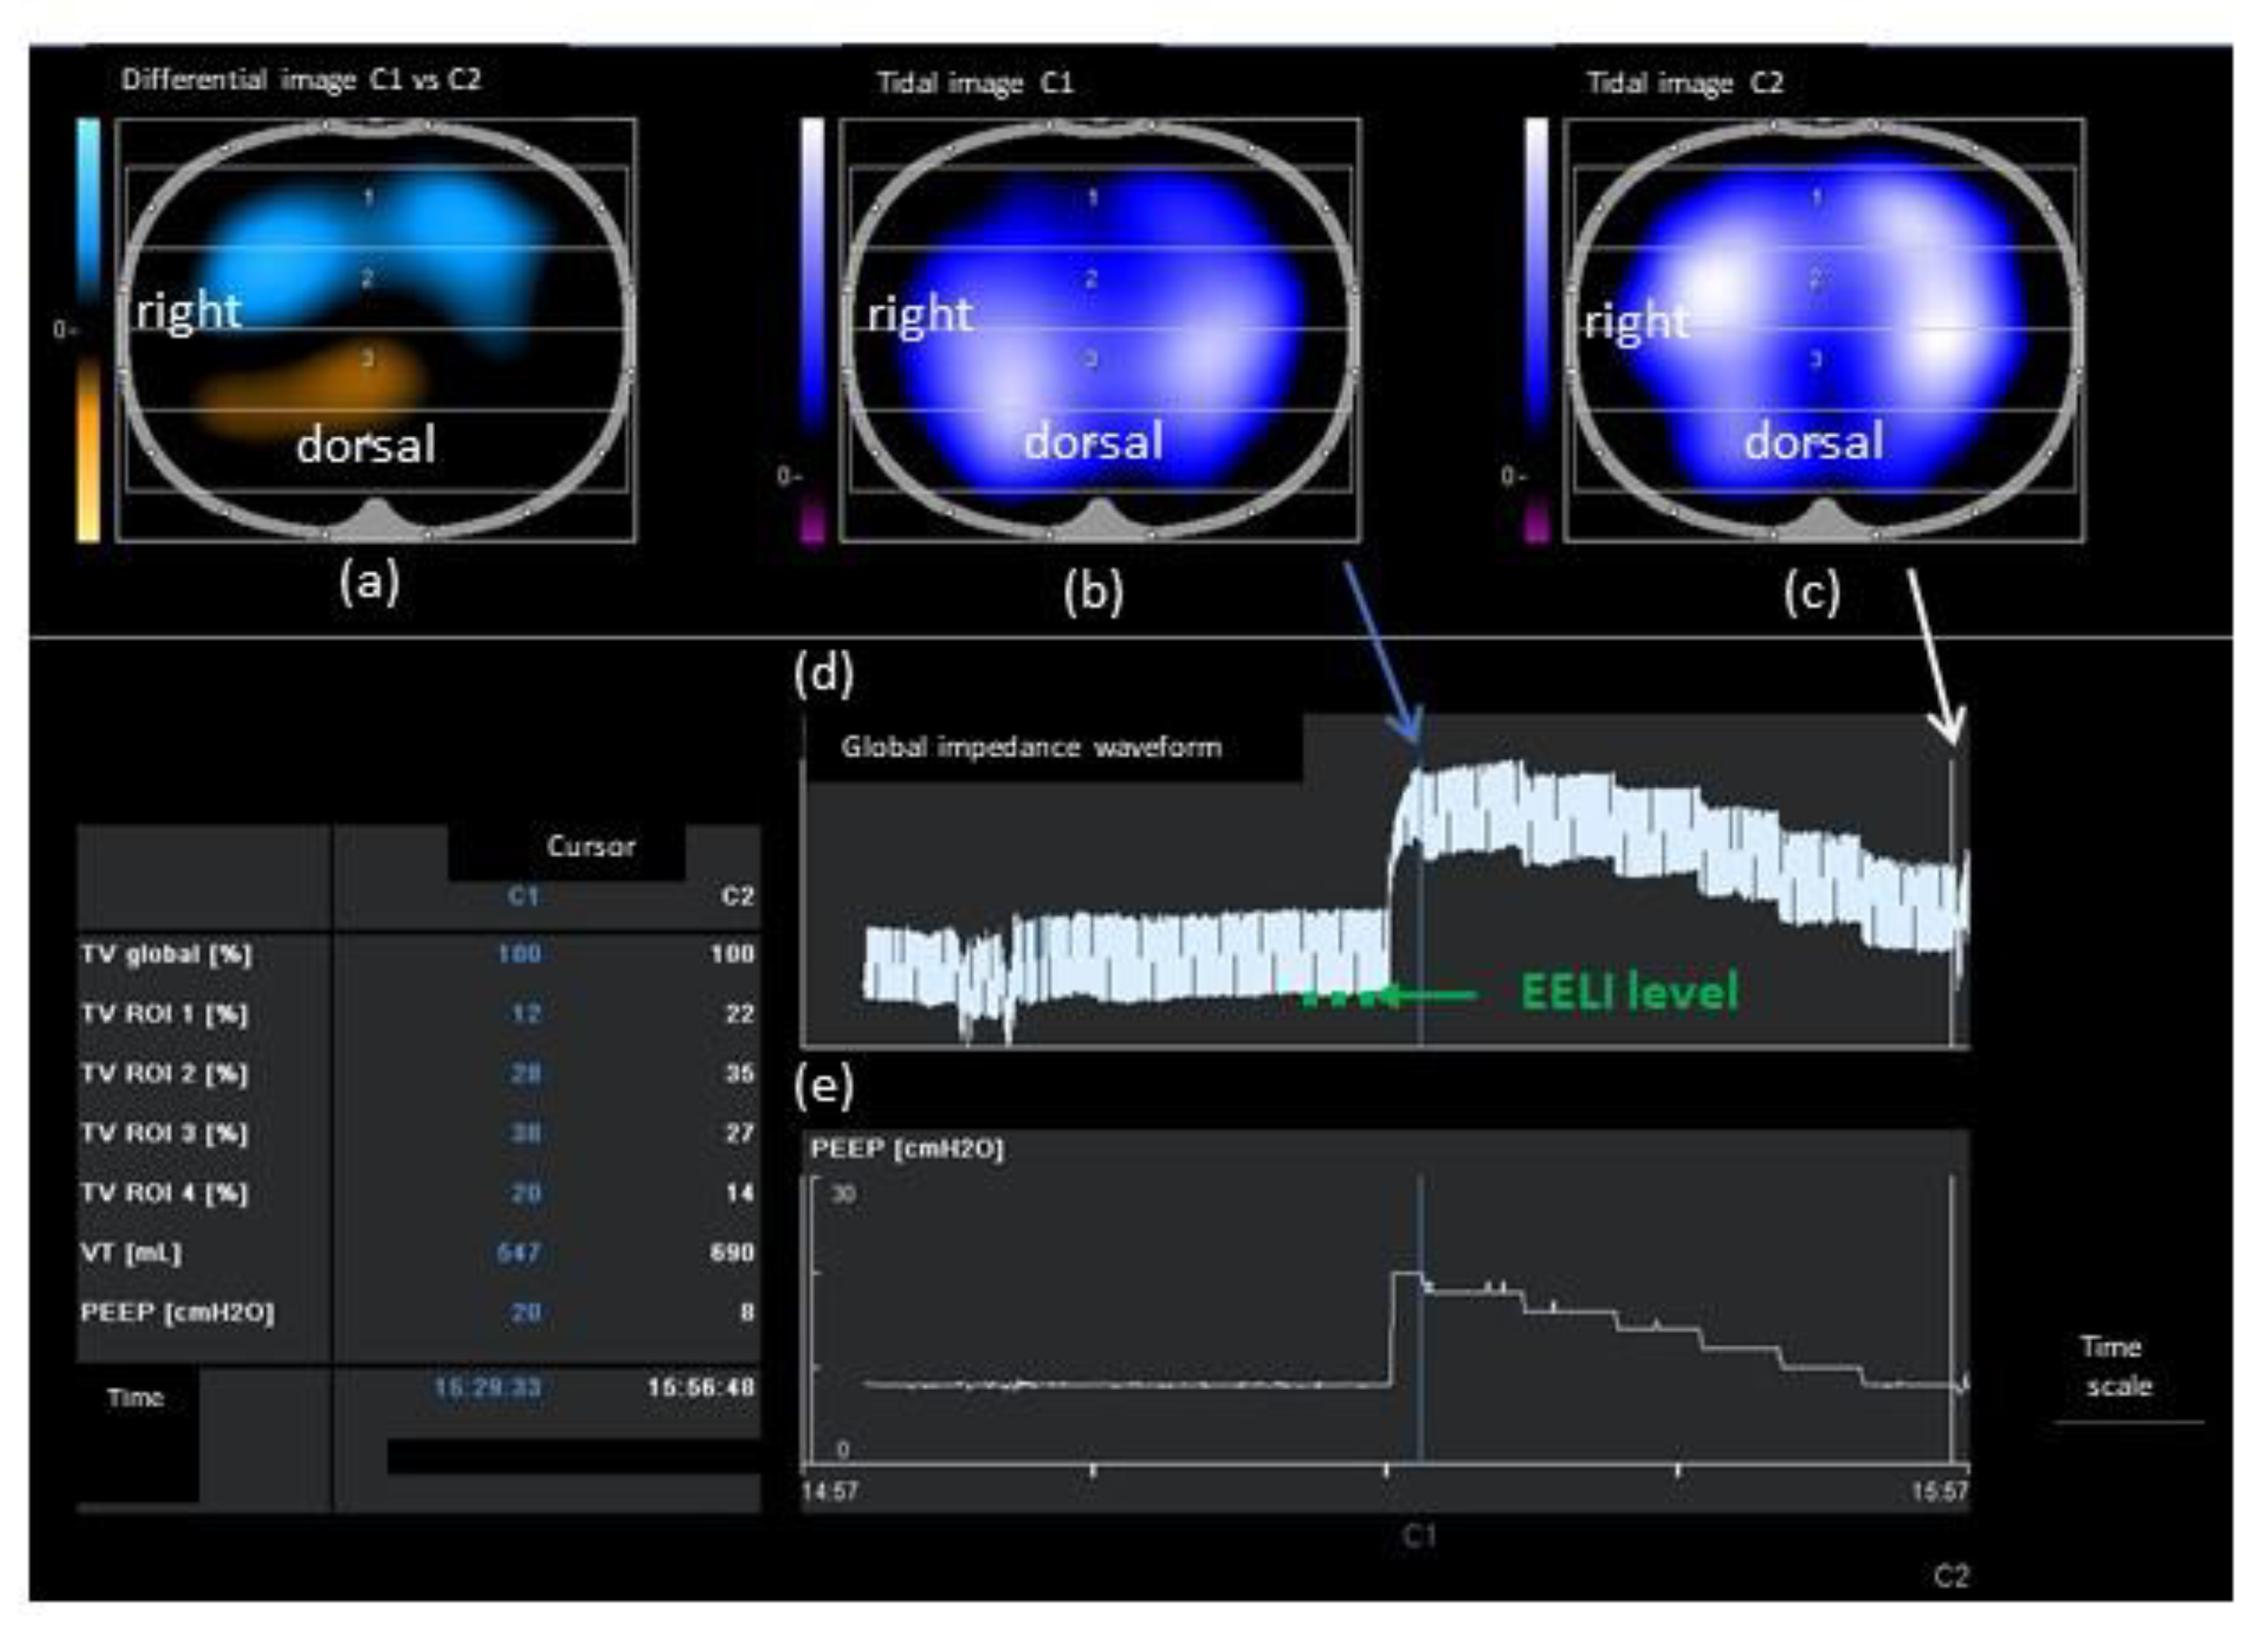

2.3. Individualized PEEP Setting by EIT (PEEPONLINE)